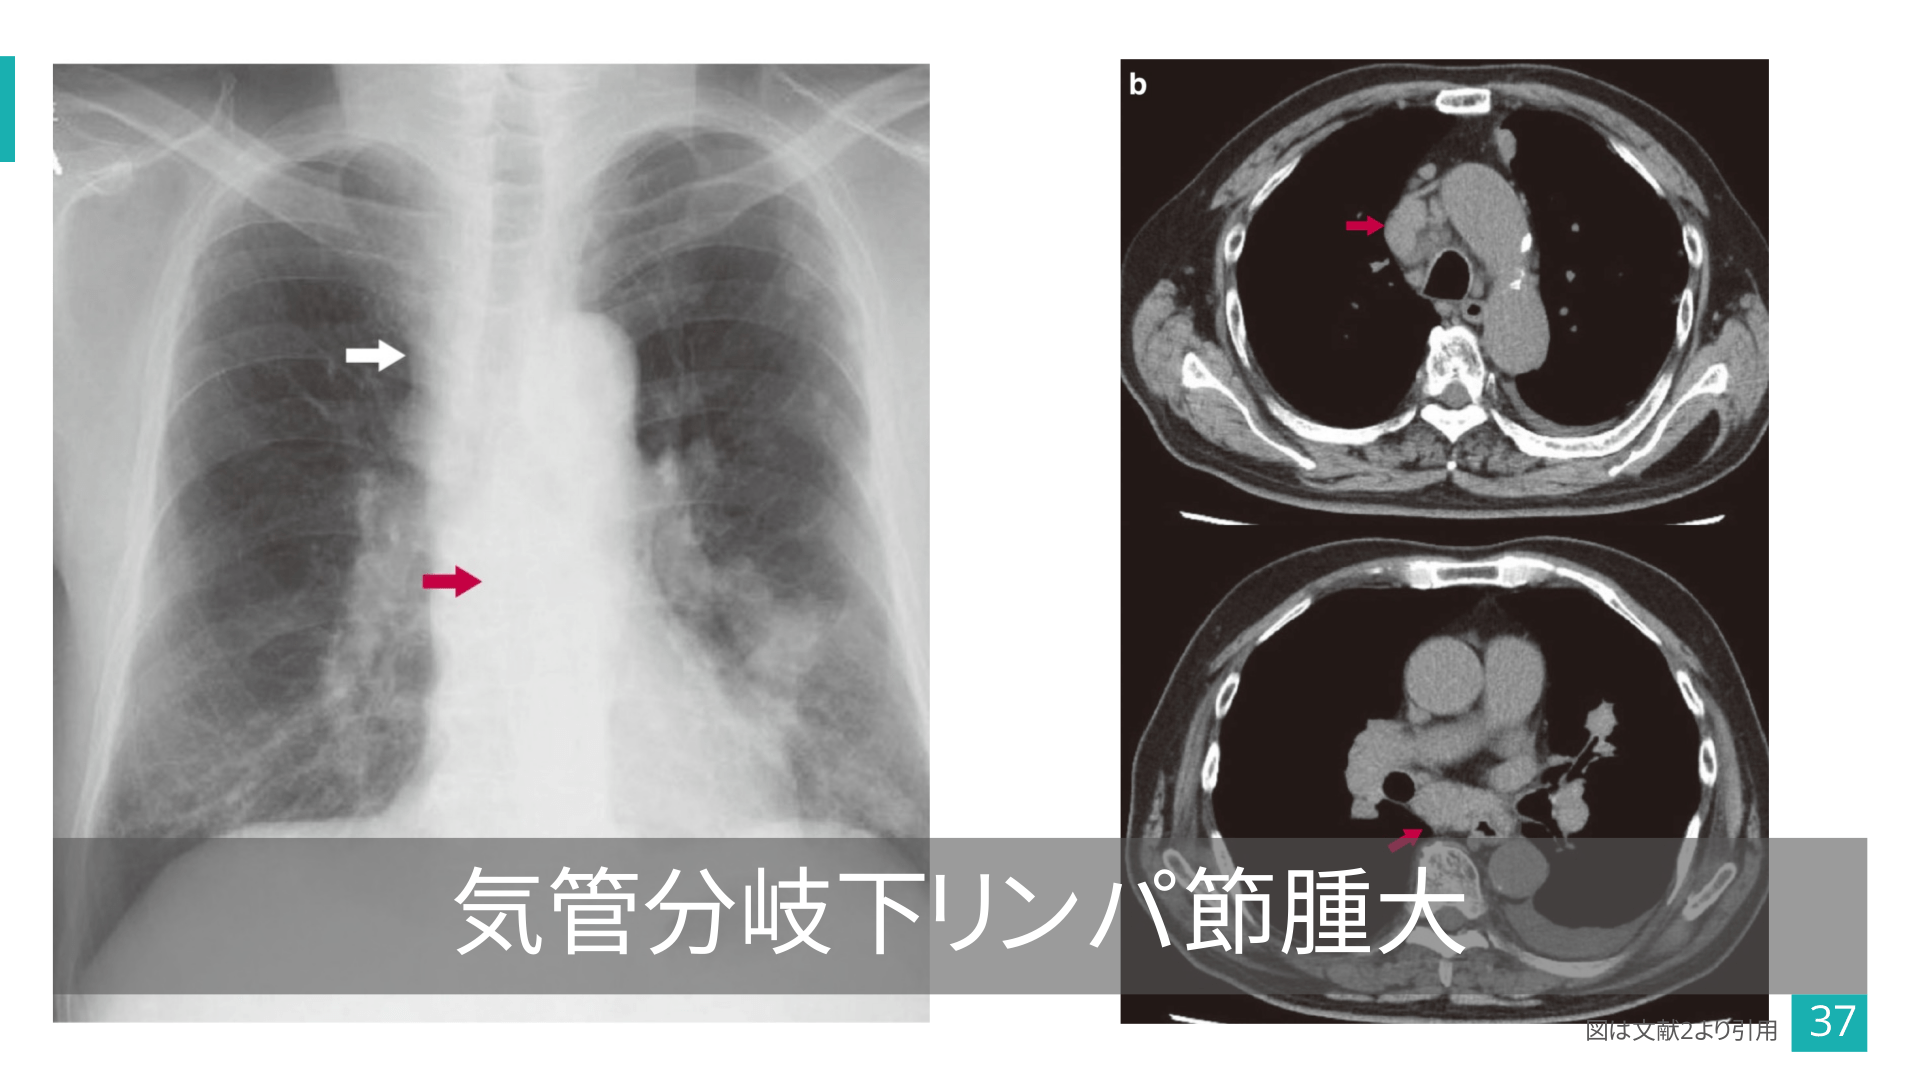

#36.

図は文献2より引用 36

#37.

気管分岐下リンパ節腫大 図は文献2より引用 37